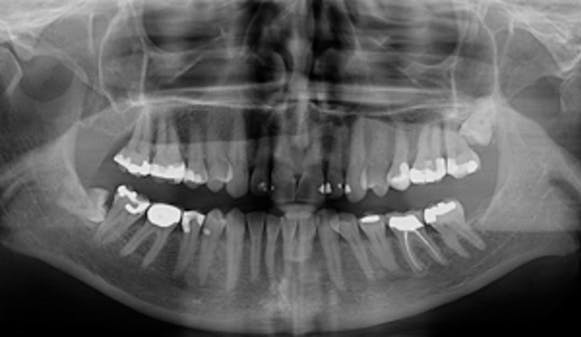

Undersøkelse hos tannlege eller tannpleier bør gjøres årlig, og kan avdekke sykdom i munnhulen…

De fleste forbinder tannlegebesøket med en sjekk etter hull i tennene. En full undersøkelse kan avdekke mye annet...